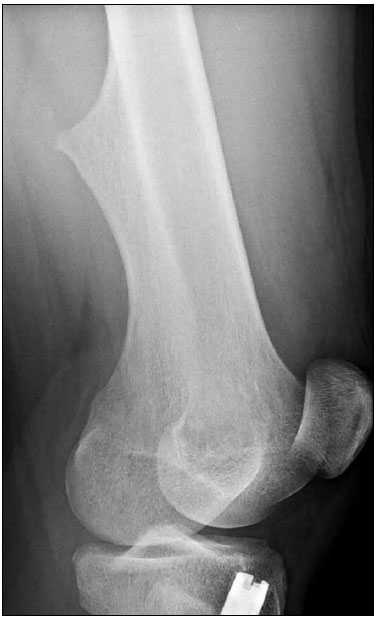

Plain radiographs of the knee are shown.

Along with mild soft tissue swelling in the distal thigh, the radiographs show an eccentric cortical outgrowth from the distal femur, directed away from the joint (A and B). The rod and nail present in the proximal tibia is related to a prior fracture.

The image findings are classic for osteochondroma. This cartilage-capped bony projection may arise from the external surface of any bone of cartilaginous origin. However, osteochondromas most commonly occur in the long bones. Similar to the physeal growth plate, an osteochondroma ceases to grow at puberty; cartilage decreases in thickness and undergoes ossification.